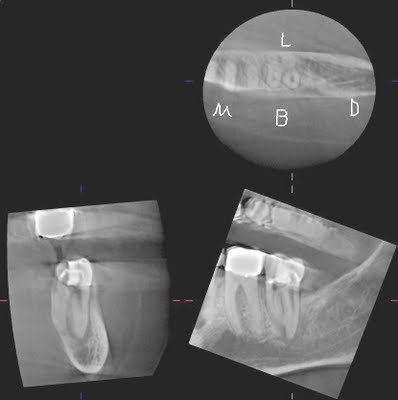

The CBCT clearly shows us that a perforation has been created (red arrow), and the additional canal/root is lingual to the DB canal. A sagittal view, provided only by CBCT, can provide information that is not available by conventional radiography.

With these images, the 4th canal is easily located within minutes of opening the tooth.